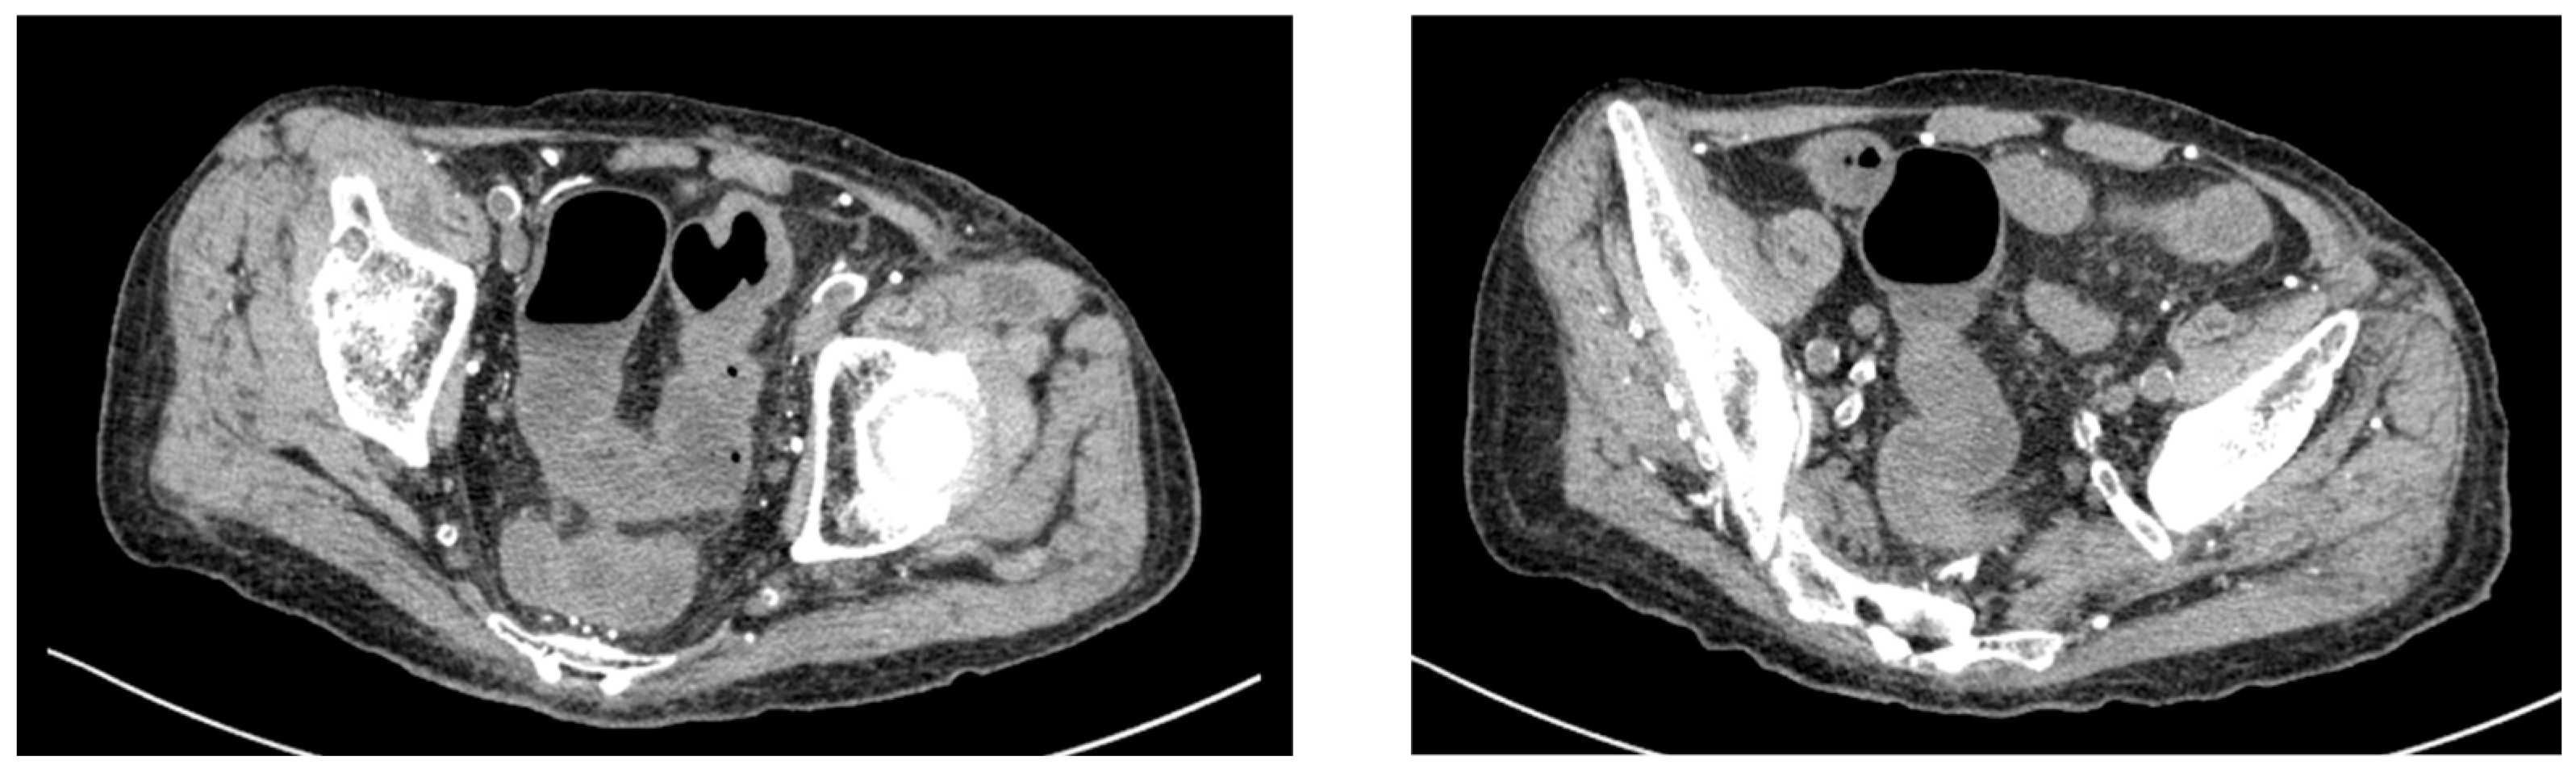

Conservative management was initiated with bowel rest, loperamide, and probiotic supplementation. The patient showed partial improvement with diarrhea frequency decreasing to 5 episodes per day by day 18. Lower gastrointestinal endoscopy was performed on day 18, revealing increased vascular permeability and mild erosions in the colon (Figure 3). Histological examination of colonic biopsies demonstrated a markedly thickened subepithelial collagen band measuring 23 μm, significantly exceeding the diagnostic threshold of 10 μm for collagenous colitis. On hematoxylin and eosin staining, eosinophilic homogeneous material was observed in the subepithelial region beneath the surface epithelium. Elastica Masson staining clearly demonstrated the extent of collagen fiber deposition as a continuous blue-stained band. The crypts maintained normal architecture without distortion or atrophy. These histopathological features, combined with the thickened subepithelial collagen band, confirmed the diagnosis of collagenous colitis (Figure 4). Lymphocyte infiltration was scarcely observed in the surface epithelium.

An important differential diagnosis in this patient is chronic uremic colitis associated with his long-term hemodialysis status. Chronic uremic colitis typically presents with colonoscopic findings of mucosal ulcerations and hemorrhagic changes, distinct from the microscopic findings observed in collagenous colitis. In our patient, colonoscopy revealed only increased vascular permeability and superficial erosions without typical uremic colitis findings. Furthermore, the acute onset of symptoms 16 days after paclitaxel initiation, rather than a chronic or progressive course, strongly suggested drug-induced etiology rather than uremia-related changes. The patient had been on stable hemodialysis for 20 years without prior gastrointestinal symptoms, which further supports paclitaxel as the causative agent rather than his underlying renal condition.

Figure 3. Colonoscopic findings on day 18 of hospitalization. The endoscopic images reveal increased vascular permeability manifested as prominent vascular patterns (yellow triangles).